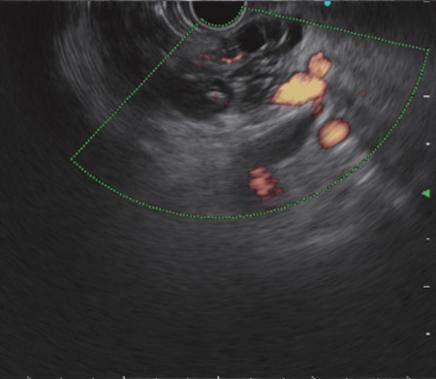

超声内镜(EUS):即内镜和超声相结合的消化道检查技术,将微型高频超声探头安置在内镜顶端,当内镜插入体腔后,在内镜直接观察消化道黏膜病变的同时,可利用内镜下的超声行实时扫描,可以获得胃肠道的层次结构的组织学特征及周围邻近脏器的超声图像,从而进一步提高内镜和超声的诊断水平。

简单来说,医生在使用超声内镜进行检查时,发现病灶,可直接诊断病变的起源层次,并可根据大小、回声特点等初步判定肿瘤性质,是生理性改变还是病理性改变,是器质性改变还是功能性改变等等。

电子凸阵扫描

PowerFlow模式

ColorFlow模式

H-Flow模式超声内镜的展望

随着超声内镜技术在临床的普及,其应用越来越广泛,尤其对于消化道肿瘤的术前分期,明确消化道早癌的浸润深度,合理把握内镜下微创治疗的适应症起到重要作用。有了超声内镜这一有利武器,使得许多疑难复杂的消化系统疾病的诊断和治疗变得容易,从而使市中心医院对消化系统疾病的诊治迈上了一个新台阶。